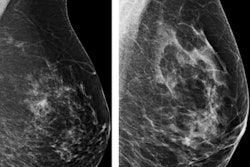

Young women at high risk of breast cancer due to a family or personal history of the disease or having dense breasts benefit from regular mammography screening starting at age 30, according to a study published online September 18 in the Journal of the American College of Radiology.

The researchers stratified patients by five-year age intervals, availability of prior mammograms, and the following risk factors for breast cancer: family history of breast cancer, personal history of breast cancer, and dense breasts.